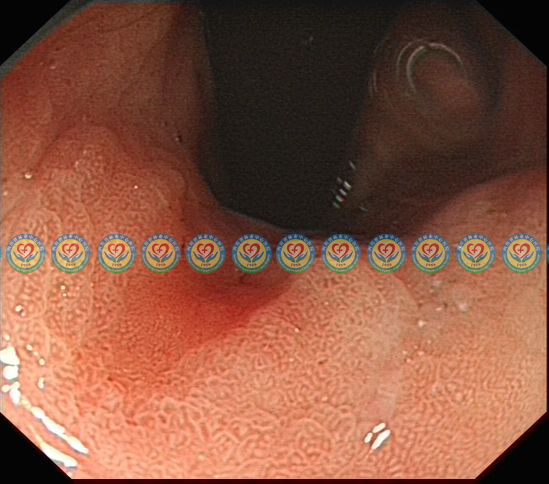

精查胃镜,靠近病变,弱放大观察粘膜表面腺管结构